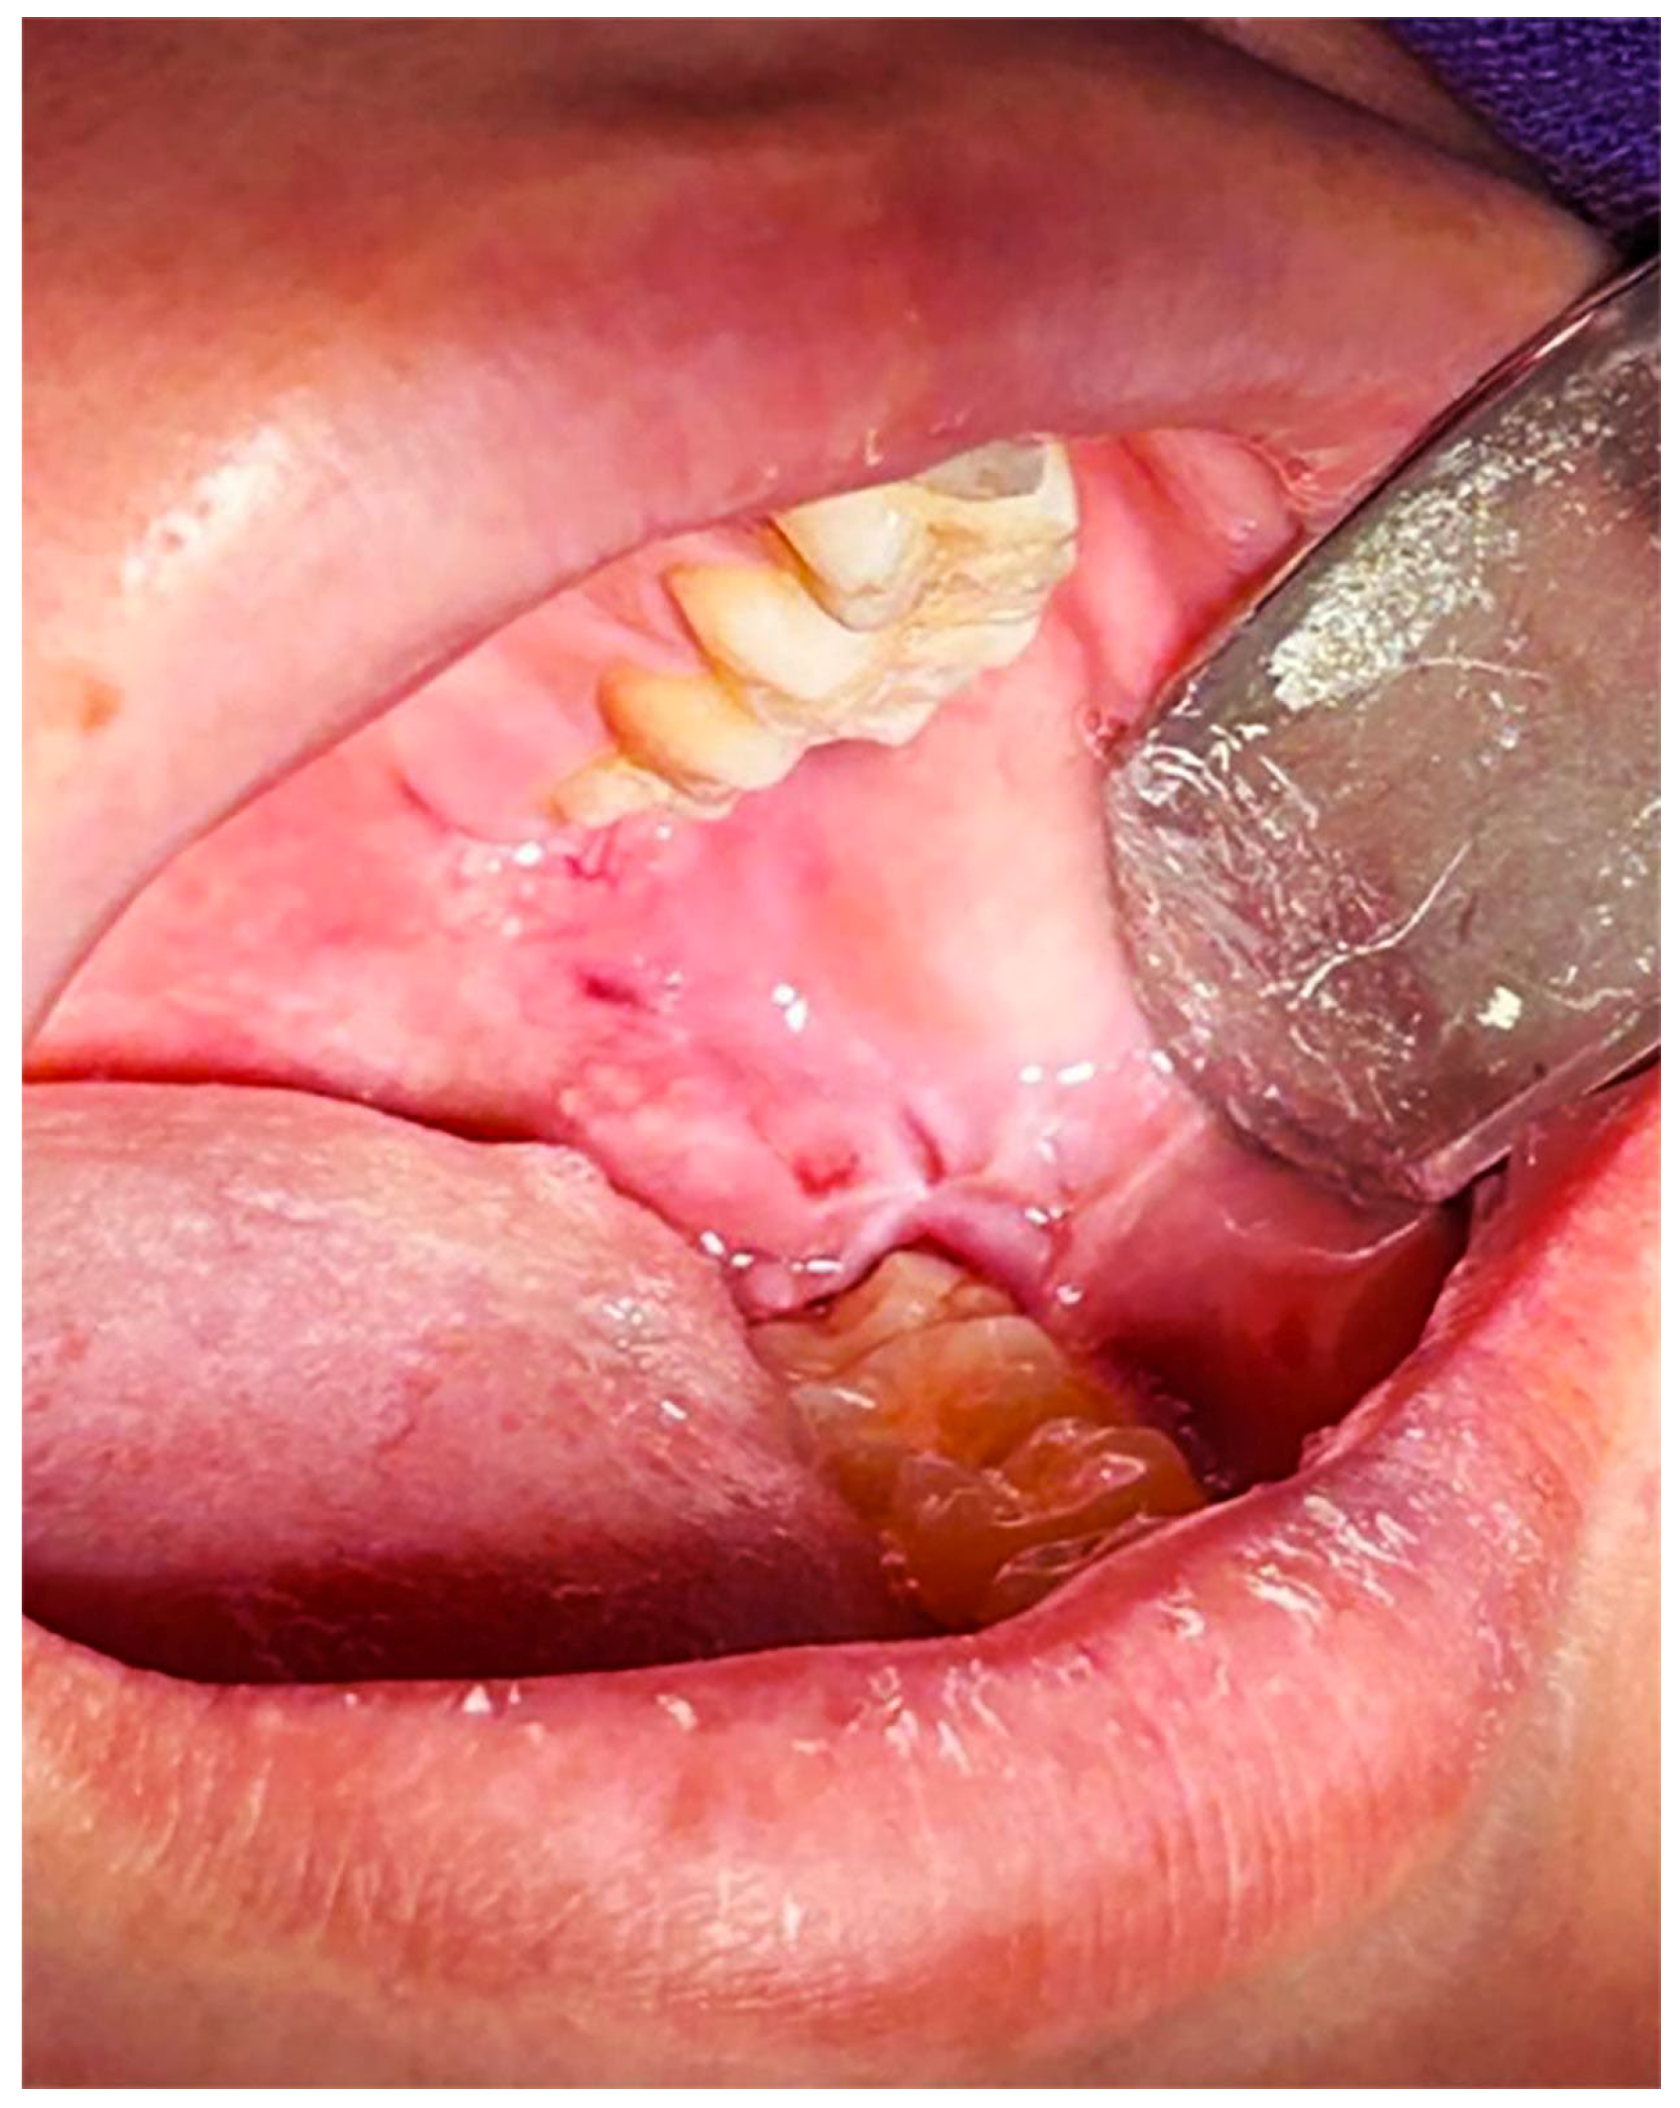

Although OS has been linked to various systemic (diabetes, cardiovascular diseases) and oral conditions (periodontal disease, lichen planus) [26,27,36,37,38,39,40,41,42,43,44]. In the case of ITMs, redox imbalance could potentially manifest clinically as an enhanced inflammatory response and postoperative pain, which might be more pronounced in patients with metabolic disorders than in those without. Table 1 presents the expression of biomarkers associated with OS in oral and systemic diseases, while Figure 1 illustrates a clinical case of a patient with Type II Diabetes Mellitus and pericoronitis associated with an ITM; in this specific instance, the clinical presentation is accompanied by altered oxidative stress markers and reduced TAC.

Figure 1.

Representative clinical case of a thirty-year-old male with a clinical diagnosis of pericoronitis and type II diabetes mellitus. This image is included for illustrative purposes to depict the inflammatory condition associated with altered oxidative stress markers, specifically MPO and MDA.